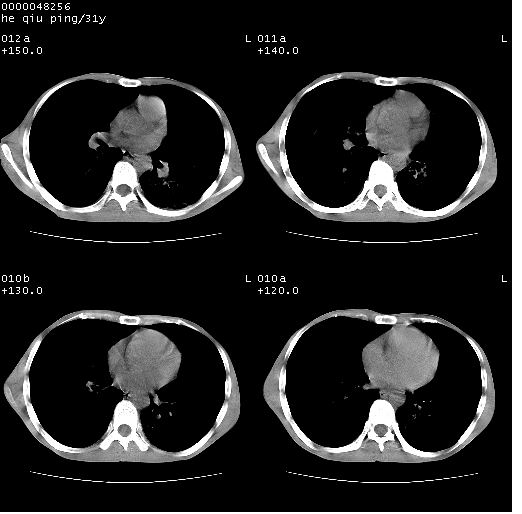

标题: CT13402:M,31Y。肺结核伴空洞形成? [打印本页]

标题: CT13402:M,31Y。肺结核伴空洞形成?

咳嗽半月余,消瘦体质,呼吸音弱。无其他病史。cr:肺转移瘤待。

双上肺多发空洞,双飞散在分布大小不一的片状结高密度影节状大片状高密度影。符合结合肉芽肿形成及空洞形成。

双侧弥漫性病变,双上叶尖后段、下叶北段见多个空洞,多见于结核感染。右中叶及双下叶斑片状,结节状影,考虑为肉芽肿形成及支气管播散。但由于患者消瘦体质,抵抗力低下,若继发感染,如金葡菌肺炎也有可能。

考虑为:两肺结核伴多发空洞形成、支气管播散。

两肺继发性结核伴多发空洞形成!不除外合并霉菌感染!

结核空洞并播散,玫瑰花簇征。

病灶多形性,有空洞形成。考虑肺结核伴空洞形成,两下肺支气管播散!